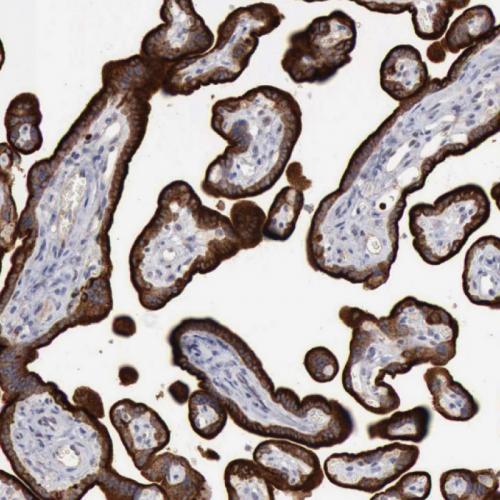

我國(guó)胃癌發(fā)病率居惡性腫瘤第2位,新發(fā)病例68萬(wàn)例,死亡49萬(wàn)例。研究表明:HP感染者均會(huì)引起慢性活動(dòng)性胃炎,在胃黏膜萎縮和腸化生的發(fā)生和發(fā)展中也起重要作用[1],HP感染和胃癌的發(fā)生密切相關(guān),根除HP是預(yù)防胃癌的有效措施。IHC染色特異性強(qiáng)、靈敏度高、陽(yáng)性準(zhǔn)確性高、易于判讀,便于各級(jí)醫(yī)院病理科開(kāi)展業(yè)務(wù),特別適合胃鏡活檢標(biāo)本量較大的情況,值得推廣[2-3]。